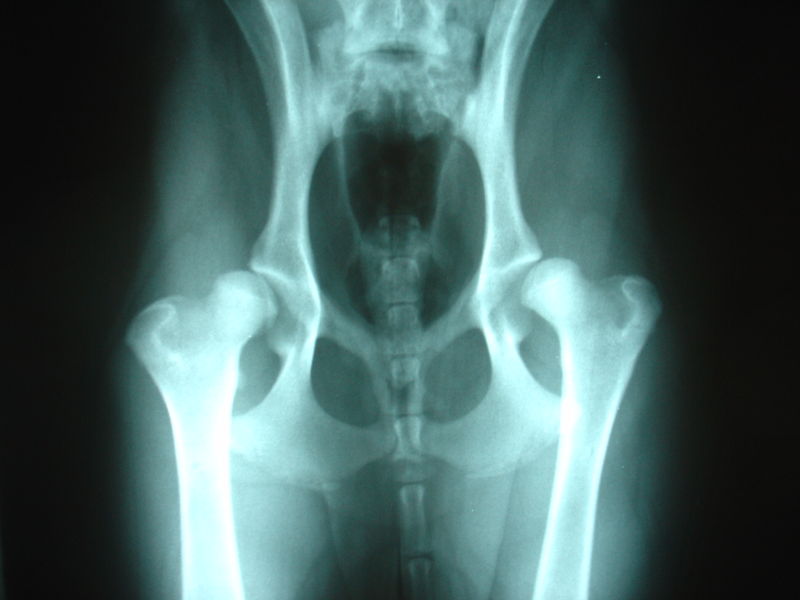

ДТБС у собак: рентгенограммы

ДТБС: степень "А" — норма